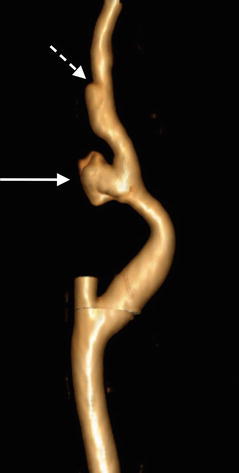

Axial CTA image through the neck in a 24-year-old male following blunt motor vehicle trauma shows a psuedoaneurysm (dashed arrow) arising from the medial aspect of the cervical left internal carotid artery (arrow)

Coronal CTA image reveals an intimal dissection flap (dashed arrow) distal to the site of pseudoaneurysm formation (arrow)

3D volumetric CTA image of the internal carotid artery with external carotid artery branches removed reveals irregular contour of the ICA pseudoaneurysm (arrow). More distally, ICA dissection manifests as focal contour abnormality of the vessel (dashed arrow)